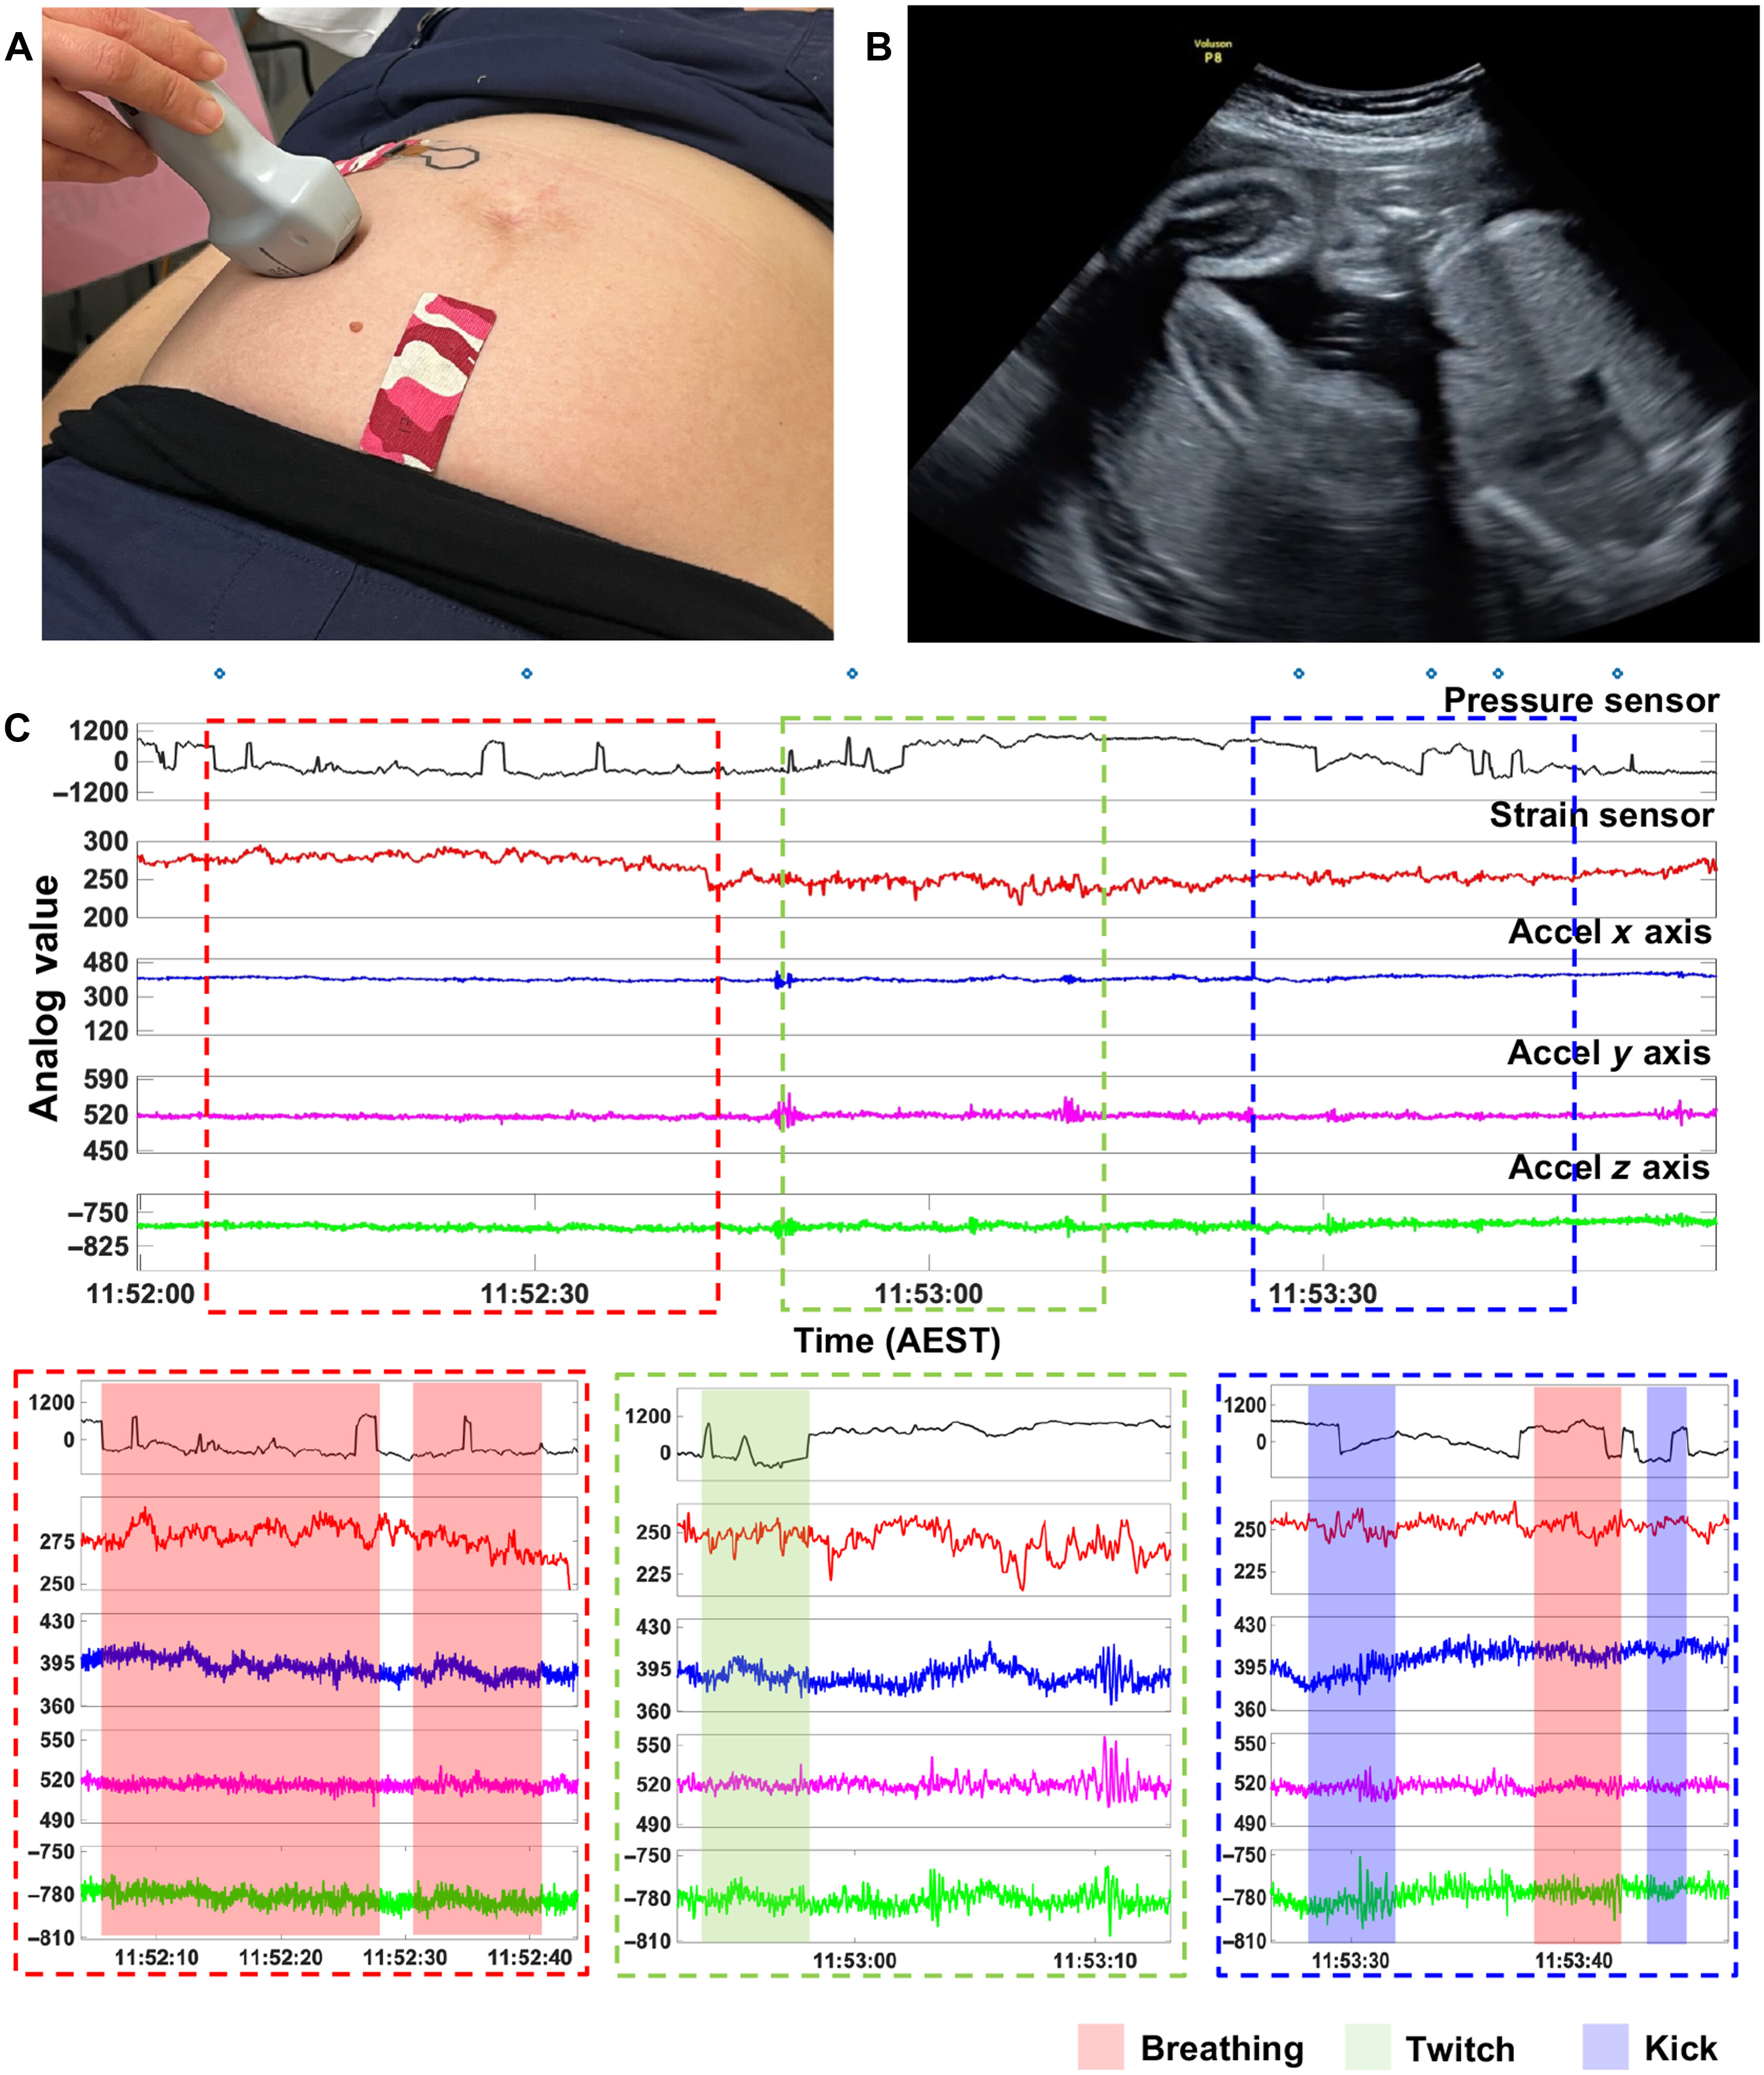

为验证设备的临床实用性,团队在澳大利亚莫纳什健康中心开展了临床试验,纳入59名孕周28-37周的孕妇,所有孕妇无胎儿畸形、妊娠并发症。试验中,孕妇佩戴贴片,同时由专业超声医师实时标注胎动,对比贴片监测结果与超声“金标准”。

莫纳什大学研发的这款监测贴片之所以能突破传统局限,核心在于“AI算法+双传感器”的协同设计——既解决了“全方位捕捉胎动信号”的硬件难题,又攻克了“区分胎动与母体活动干扰”的算法瓶颈,让10-14cm2的贴片实现“小体积、大功能”。

2.双传感器组合:广角捕捉+精准定位

研究团队设计了两种互补的传感器,分别应对不同类型的胎动信号:

◆八角形金纳米线-应变传感器:负责全方位捕捉

不同于传统U型传感器只能单向感知信号,八角形设计(7条直边+8个角)让传感器具备各向同性灵敏度——无论胎儿在母体腹部左侧、右侧还是下方活动,产生的腹部皮肤拉伸应变都能被均匀捕捉。

在2D模拟腹部模型中,它的监测范围可达77cm2,3D模型中更是扩展到217cm2,相当于用一个传感器覆盖半个腹部,解决了传统可穿戴设备需多个传感器拼接的繁琐问题。

◆叉指电极-压力传感器:负责精准定位

针对胎儿抽搐、打嗝等局部发力的胎动,研究团队搭配了叉指电极结构的压力传感器——它的局部监测灵敏度极高,能精准定位胎动发生的具体位置,但监测范围较小(2D模型中约13cm2),正好与应变传感器的“广角优势”形成互补。

两种传感器集成后,贴片厚度仅3mm、重量约3g,通过医用双面硅胶贴附着在孕妇腹部,可直接贴合皮肤,甚至能随腹部弧度弯曲,佩戴时不影响穿衣、行走,实现“无感监测”。